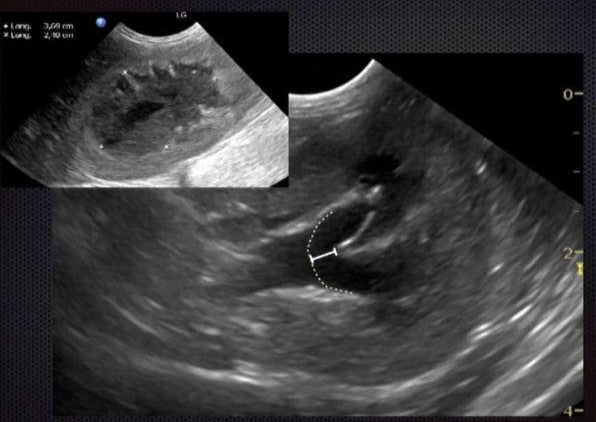

Imagerie Des Obstructions Hautes de l’appareil Urinaire Chez Le Chat

- Attitude face à une suspicion d’obstruction urinaire haute.

- Avoir une démarche raisonnée et savoir choisir les bons examens complémentaires.

- Maitriser les clés de l’échographie pour diagnostiquer une lithiase urétérale.

- Connaitre le principe les avantages et les limites des autres techniques d’imagerie médicale lors d’obstruction haute de l’appareil urinaire.